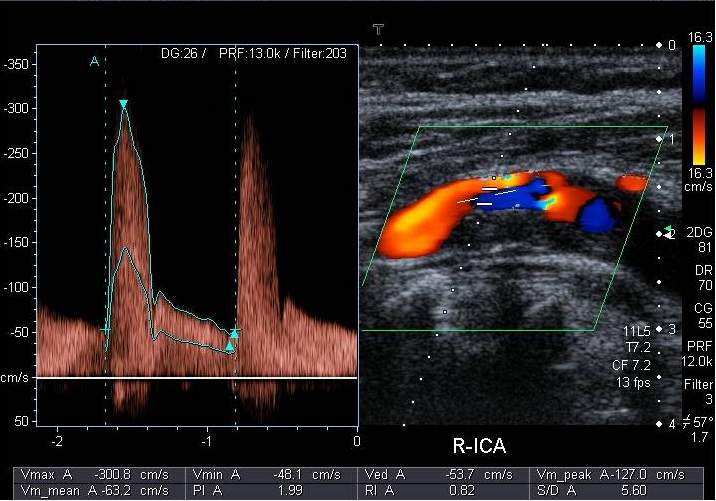

8.2.2.3.1. Stroke – cerebrovascular diseases

In the majority of the cases, stroke is causes by the atherosclerotic lesion of the supplying arterial system of the brain. Ultrasound examination can reliably depict a long segment of the four main extracranial large vessels supplying the brain. Fortunately, most atherosclerotic lesions that causes cerebrovascular symptoms are to be found in the carotid bifurcation and therefore they can be well diagnosed on carotid US examinations. Besides depicting plaques, US can measure their size and assess their composition. Lipid-rich plaques that are covered with a thin, easily rupturing fibrotic cap are considered instable, but inhomogeneous structure and irregular surface are also a poor prognostic factor. Exulceration, a consequently appearing excavation on the surface of the plaque carries the highest risk for embolization. Color Doppler examination can help precisely define the contours of plaques. It can clearly depict the residual lumen of the narrowed arterial segment and it is able to confidently differentiate between complete obstruction from high grade stenosis. Contrast enhanced ultrasound examination can show the angiogenesis at the basal part of instable plaques as well as MRI examination. One of the main diagnostic goals of cerebrovascular imaging is to determine the grade of stenosis of the internal carotid artery, since the risk of stroke grows parallel with the grade of the stenosis, which can be avoided with reconstructive surgery or with stent implantation. A 50% diameter decrease is considered the limit at which point a stenosis counts as hemodynamically significant. Below this the grade of stenosis can be well estimated with 2D planimetric measurements. Above this level stenotic lesions are quantified by their hemodynamic effect, based on the measurements of flow velocity increase. If a significant stenosis is discovered, the patient must be closely followed. At a stenosis of about 70% surgical or interventional procedure should already be considered. In these cases, or when diagnosis is equivocal, it is important that the duplex sonography is followed by an imaging method that can visualize the cerebrovascular system in full.

Image

Duplex ultrasonography with targeted Doppler measurement

Contrast enhanced MR-angiography

Fig. 14., 15.: Arteria carotis interna stenosis